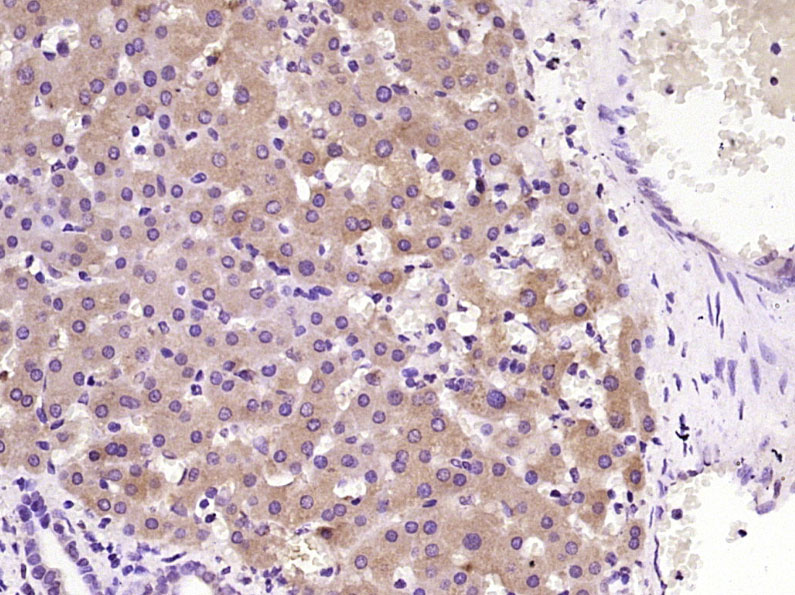

| 应用 | 已检合格种属 | 预测种属 | 推荐稀释比例 |

|---|---|---|---|

| IHC-P | Human | 1:100-500 | |

| IHC-F | Human | 1:100-500 | |

| IF | Human | 1:100-500 |